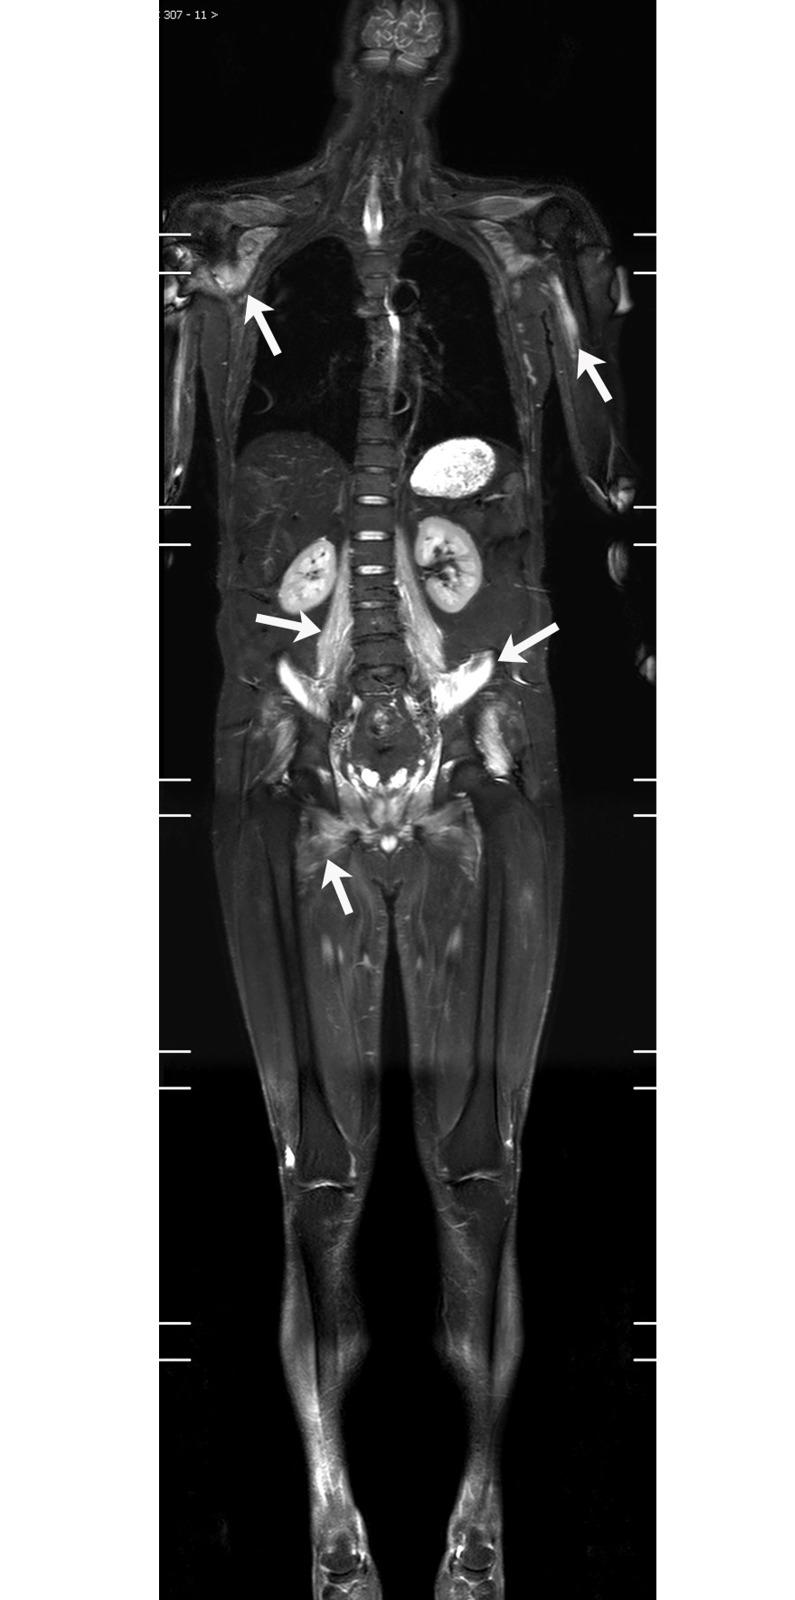

An efficacy analysis of whole-body magnetic resonance imaging in the diagnosis and follow-up of polymyositis and dermatomyositis.

The study included 129 patients (30 PM cases and 99 DM cases). Of them, 81.4% (105/129) showed a visible inflammatory muscular edema on their WBMRI; 29.5% (38/129) had varying degrees of fatty infiltration (9 cases with clear muscular atrophy). Of the 66 newly diagnosed patients, the positive rates of WBMRI, muscle biopsy, serum creatine kinase test and EMG were 86.4% (57/66), 92.4% (61/66), 71.2% (47/66) and 71.1% (32/45), respectively. There was no significant difference in the positive rates between WBMRI and muscle biopsy (X2 = 1.28, P = 0.258). The WBMRI had a higher positive rate than both serum creatine kinase test (X2 = 4.53, P = 0.033) and EMG (X2 = 3.92, P = 0.047). In addition to muscular changes, WBMRI also detected interstitial lung disease (ILD) in 38 cases (29.5%), osteonecrosis in 15 cases (11.6%), and neoplastic lesions (5 malignant; 7 benign) in 12 cases (9.3%). Of the 61 patients who underwent routine chest CT examinations, the WBMRI and CT revealed ILD in 29 cases and 35 cases respectively. There was no significant difference in the sensitivity between WBMRI and CT (p = 0.146).

WBMRI is a sensitive, non-invasive and efficient imaging method. It comprehensively displays the extent of muscular involvement in PM/DM patients, and it has the ability to diagnose other associated extra muscular diseases, such as ILD and systemic malignancy. WBMRI can also help screen steroid-induced osteonecrosis.